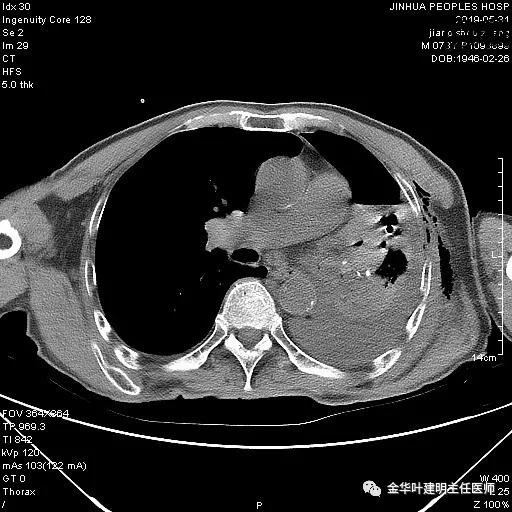

6.15上午:24小时胸管引流出血性液250ml;复查胸部CT示: